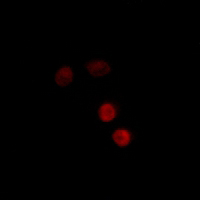

Application

| WB, IF/IC |

| Dilution | WB~~WB (1/500 - 1/1000), IF/IC (1/100 - 1/500) IF/IC~~N/A |

| Cellular Location | Nucleus. Cytoplasm. Note=Nucleoplasmic shuttling is both hormone- and cell cycle-dependent. On hormone stimulation, retained in the cytoplasm in the G(1) and G(2)/M phases [Isoform 4]: Mitochondrion outer membrane |